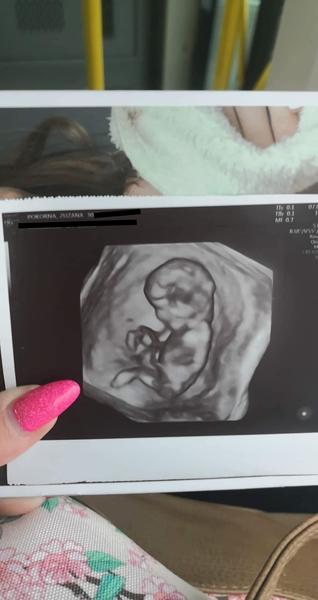

@pipi_puncocha To je super! V kolikátém TT jsi byla na screeningu?

@ivca_ch ve 13tt, přesně teda 12+4. 😊 termín máme 14.11.

@pipi_puncocha já jdu 12+6 dle MS, tak pořád přemýšlím, jestli to není brzo 🙂

@ivca_ch proč myslíš? Ten UZ se má dělat mezi 12. a 14.tt, to jdeš úplně uprostřed toho rozmezí.😉 mně takto v nemocnici objednali a byla jsem překvapená kolik toho bylo vidět (pan doktor tam prohlížel mozkové hemisféry, oční čočky, srdíčko..)